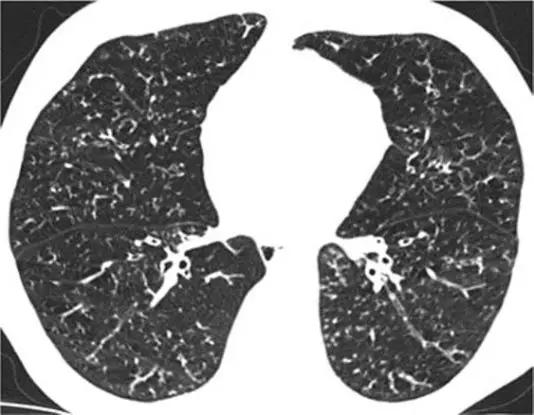

6、结节影

HRCT上的结节性形态的特征是存在许多圆形密度影,直径范围从2 mm到1 cm,微结节的直径小于3 mm [38]。除临床情况和辅助检查结果外,鉴别诊断主要基于解剖分布的三种不同模式:淋巴分布、随机分布和小叶分布。淋巴分布的特征是沿支气管周围血管间质,小叶间隔和胸膜下区域存在结节。随机分布显示结节,没有任何特定的站点优势。小叶小结节距胸膜表面,小叶间裂或小叶间隔几毫米。中心小叶分布进一步分为有和没有树芽状分布的结节。

6.1淋巴管分布结节

按淋巴管分布的结节典型疾病是结节病。结节主要位于肺门附近及中上肺野。

*结节病 上叶水平的HRCT表现为“无树芽征的结节状结节”,其特征是小叶间隔,裂隙,支气管血管束和胸膜周围存在淋巴小结节。

矽肺病的是结节病的模仿者,通常表现为淋巴管和小叶中心尖锐的微结节,范围从2mm到5 mm。结节的定义清晰且密度均匀,上叶和后段为主。支持矽肺病诊断的明显发现是微结节的聚结,淋巴结的蛋壳钙化形成的团块(罕见,仅占结节的5%)病例和胸膜下假性斑块的形成,同样是基于胸膜下微结节的合并。在大多数情况下,有接触史。

*矽肺病。上叶水平的CT表现为“无树芽征的结节状影”,特征是明确定义的均质小叶结节,主要位于上叶和后段。